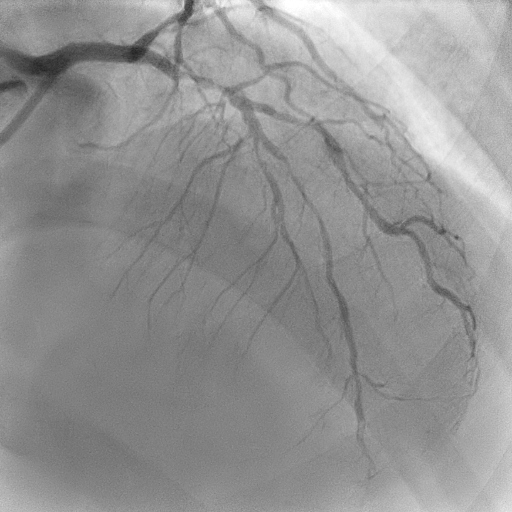

Coronary angiography revealed mild disease of the left main stem. The LAD exhibited severe proximal, mid, and distal disease of a diffuse nature. The LCx demonstrated severe mid–distal disease with a severely stenosed proximal obtuse marginal branch. The dominant RCA showed severe mid-vessel disease with significant involvement of the PL branch.

Mid–proximal LAD was sequentially prepared with SC 2.0 balloon and IVUS guidance; distal LAD underwent POBA with SC 1.5 balloon. Lesions in mid LAD and proximal LAD were refined with scoring balloons 2.5/15 and 3.5/15, respectively, treated with DCBs 2.5/30, 2.5/30 and3.5/25. A proximal Type C dissection sealed with a Fantom Encore BRS 3.0/24, post-dilated with NC 3.5/15. LCx and OM prepared with sequential SC balloons 1.5/15 and 2.0/15. Treated with DCBs 2.0/20 at proximal OM and 2.0/30 at LCx. RCA planned for staged angioplasty. Left coronaries were restudied at the time when patient was readmitted for staged angioplasty to RCA, showed excellent results. RCA prepared with POBA to the PL branch with 1.5 SC balloon, scoring balloon 2.5/15 to distal–mid RCA, followed by DCBs 2.75/40 and 3.0/30. A Type A dissection ensued in mid RCA, yet final TIMI III flow achieved.